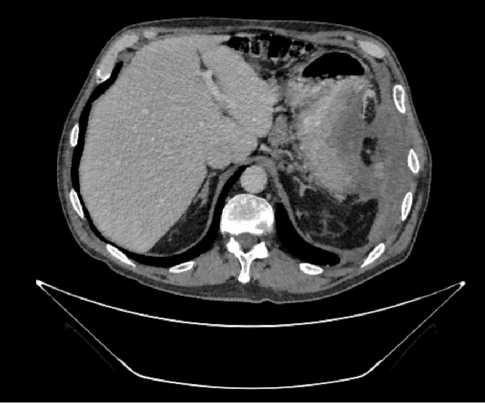

В результате обследования был установлен диагноз рака антрального отдела желудка (c)T4аN3вM1. По решению онкологического консилиума, учитывающего молекулярно-генетический профиль опухоли, а также возраст пациента, выраженность сопутствующей патологии (в анамнезе острое нарушение мозгового кровообращения (ОНМК), острый инфаркт миокарда (ОИМ), фибрилляция предсердий (ФП), постоянная форма), ограничивающей проведение ПХТ, была начата ИТ 1 линии пембролизумабом. С сентября 2019 г. по декабрь 2021 г. проведено 29 циклов ИТ 1 линии по схеме пембролизумаб в монорежиме с максимальным эффектом частичный регресс (рис. 4). Осложнений лечения не зарегистрировано.

Рис. 4. Частичный регресс по данным компьютерной томографии органов брюшной полости на фоне иммунотерапии пембролизумабом у пациента 81 года с диагнозом метастатический рак желудка с признаками микросателлитной нестабильности (декабрь 2021 г.; выживаемость без прогрессирования составила 25+ мес.)

Fig. 4. Partial response according to abdominal CT scan during immunotherapy with pembrolizumab in an 81-year-old patient diagnosed with MSI-H metastatic gastric cancer (December 2021; progression-free survival was 25+ months)

Пациент находится под динамическим наблюдением без признаков прогрессирования процесса по настоящее время (выживаемость без прогрессирования составила 25+ мес.).